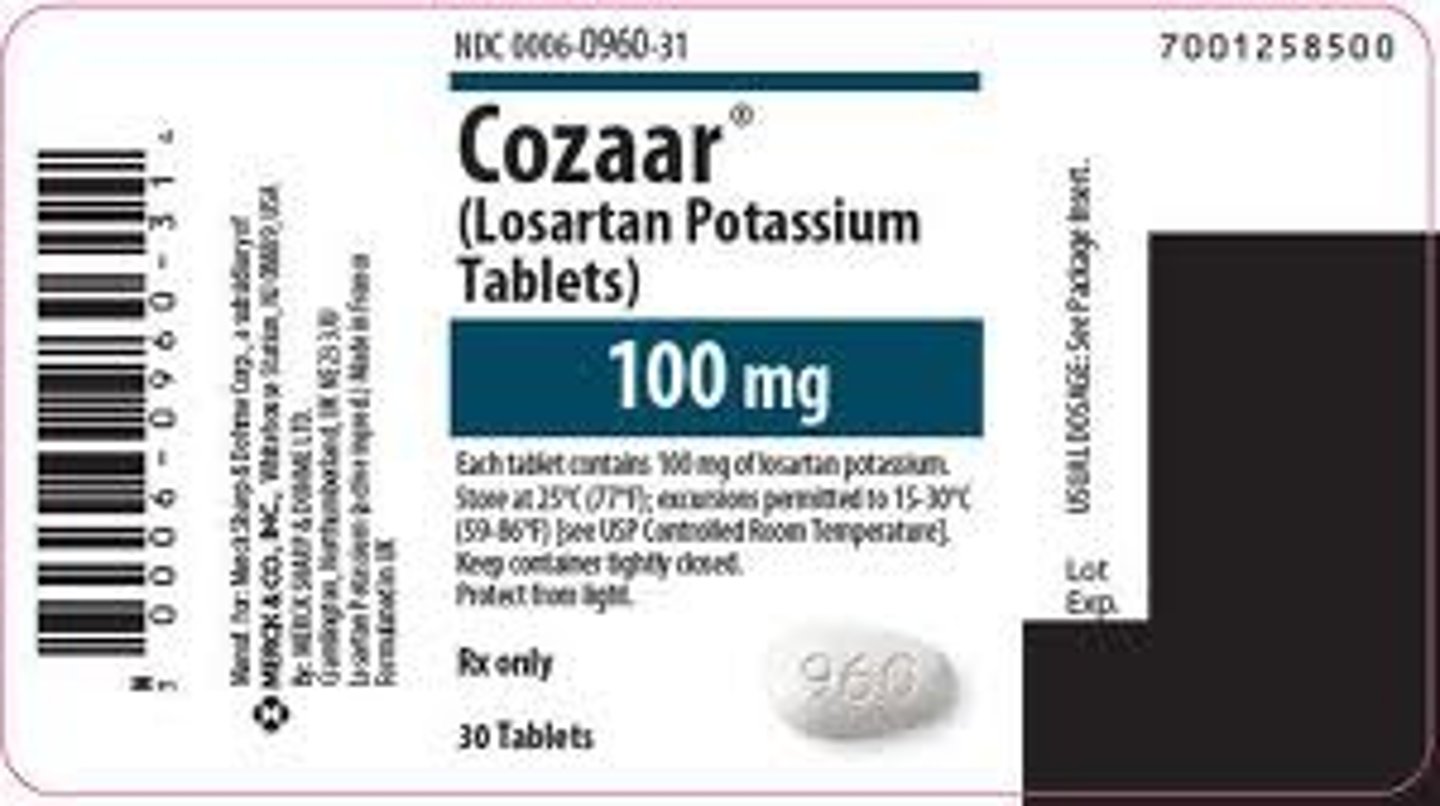

Losartan potassium

Brand: Cozaar

Class: ARB

Indication: Antihypertensive

Schedule: NCLM